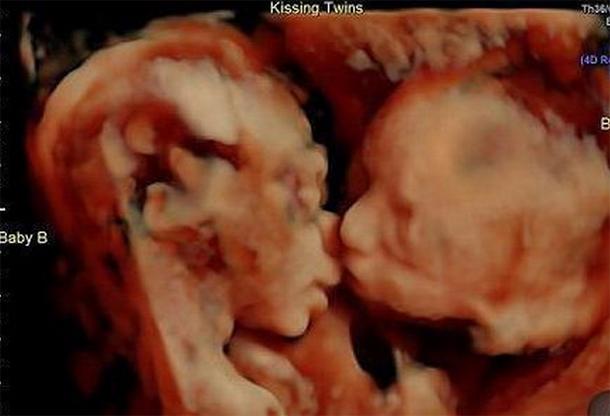

Carissa Gill, a terhessége 24. hetében a 3D/4D ultrahang vizsgálatról egy fantasztikus képpel távozott: a szkenner pont elcsípte, ahogy az iker-magzat megpuszilja egymást!

A két pici lány már most odavan egymásért; ahogy a felvételen is látszik, már az anyaméhben puszizkodnak. „Ez a legédesebb ultrahang-felvétel, amit valaha láttunk” – még az orvosokat is lenyűgözte!

Az ultrahang-kép készítői megosztották ezt a csodát az Instragamon is, a posztban pedig gratuláltak Carissának és Randynek a puszilkodós ikrekhez. A büszke anyuka pedig saját oldalára is feltette a képet, hogy az egész világgal megoszthassa: „Kismamának lenni már önmagában is a világ legcsodálatosabb érzése, hát még ha az ember ilyen megható és különleges pillanatot kaphat el, már alig várom hogy Isabella és Callie a világra jöjjön!”